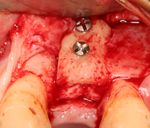

يتم اجراء جراحة الأسنان في العيادة تحت ظروف معقمة، من قبل طبيب أسنان متخصص في زراعة الأسنان و/أو جراحة الفم والفك. يتم تخدير المريض بواسطة حقنة بمخدر موضعي في منطقة دواعم السن، كما هو الحال في علاجات الأسنان العادية (في بعض الأحيان هناك حاجة بتوسيع نطاق التخدير، وفقاً لموقع الغرسات).

اذا كان العظم على استعداد لتلقي الزرع (أحيانا بعد سلسلة علاجات مسبقة)، يمكن البدء بعملية زرع الاسنان. يتم تثبيت المسامير المعدنية اللولبيه براغي، بعظم الفك. في سلسلة اخرى من العلاجات بعد فترة من ادخال البراغي، تبدا عمليات اعادة البناء عن طريق أخذ القياسات وانشاء التاج/الجسر. عندما يدور الحديث عن فترة الانتظار بين تركيب الغرسات وبين تنفيذ الاستبناء النهائي، فان هنالك اكثر من نهج واحد. النهج المتبع غالبا هو الانتظار لمدة 6 أسابيع على الأقل حتى تلتئم الانسجة، وأحيانا تصل فترة الانتظار لعدة شهور.